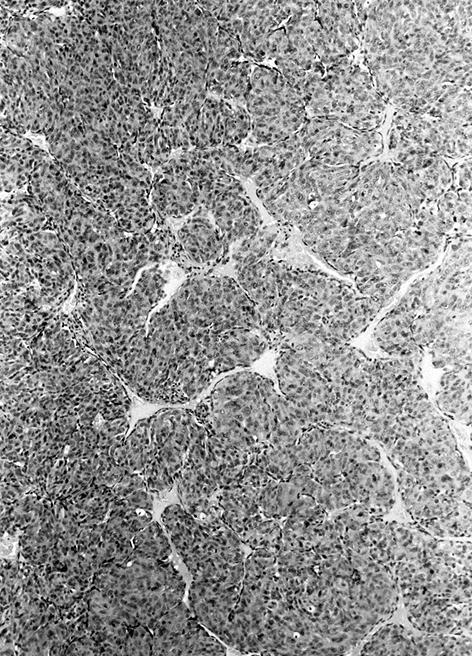

Microscopic (histologic) description

- Wide variety of morphology, can mimic any other thyroid malignancy

- Round, plasmacytoid, polygonal or spindle cells in nests, cords or follicles; often mixtures of these cells

- Stroma has amyloid deposits from calcitonin, prominent vascularity with glomeruloid configuration or long cords of vessels (Am J Surg Pathol 1995;19:642), coarse calcifications, occasional psammoma-like bodies

- C cell hyperplasia present in familial but not sporadic cases

- Microcarcinoma:

- Complex microarchitectural pattern with desmoplastic stroma, often focal amyloid deposition

- Usually a solid pattern of round, polygonal, spindled or plasmacytoid cells (Arch Pathol Lab Med 2008;132:1767)

- Often C cell hyperplasia (Am J Surg Pathol 2000;24:853)

Variants (important for differential diagnosis, most are of no prognostic importance):

- Paragangioma-like variant:

- Nested tumor cells, mimics paraganglioma (Mod Pathol 1990;3:581)

Microscopic (histologic) images

Contributed by Shuanzeng Wei, M.D., Ph.D., Joseph Christopher Castillo, M.D. and Mark R. Wick, M.D.

AFIP images

Images hosted on other servers: